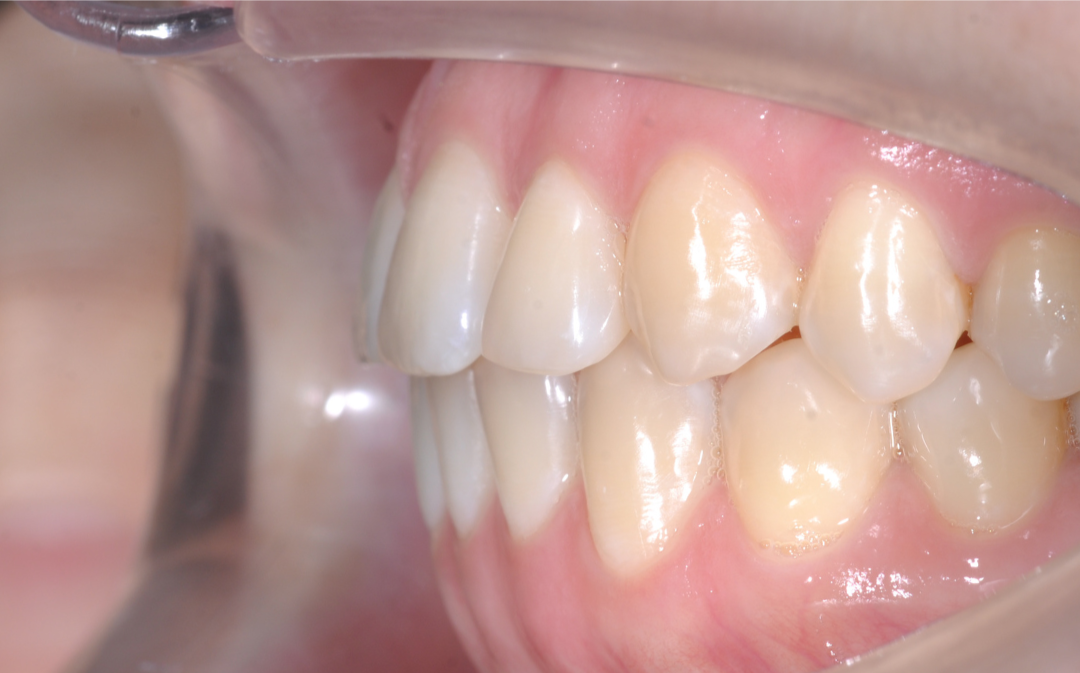

Результаты комплексного лечения

Комплексный подход команды «Архитектор Улыбок» дал закономерный результат, который был спрогнозирован еще

до старта лечения.

Здоровая улыбка

Ушел дискомфорт в суставе, исчезли боли в процессе жевания. Нижняя челюсть заняла стабильное, физиологичное положение.

Восстановилась функция

Качество жевания кардинально повысилось, процесс приема пищи снова стал комфортным.

Эстетика

Исправлен прямой прикус, восстановлена форма резцов, а улыбка стала не только красивой, но и здоровой с точки зрения биомеханики.